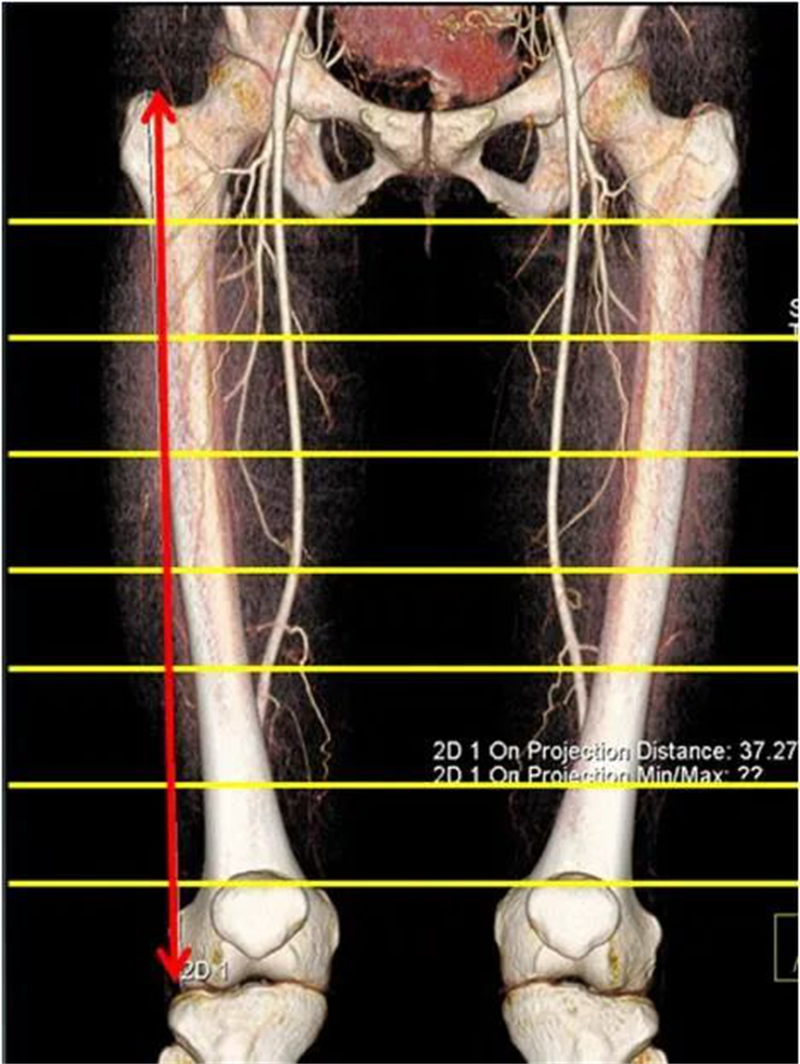

该研究采用带有 3D 重建的轴向 CT 扫描以识别股浅动脉(SFA)和 股深动脉(DFA)相对于股骨干皮层的位置,把股骨内侧划分成8个部分(A-H),股骨的长度从大转子尖端到胫股外侧关节线的长度,分为8等分(7级)。

图3 股骨的长度从大转子尖端到胫股外侧关节线的长度,分为8等分(7级)